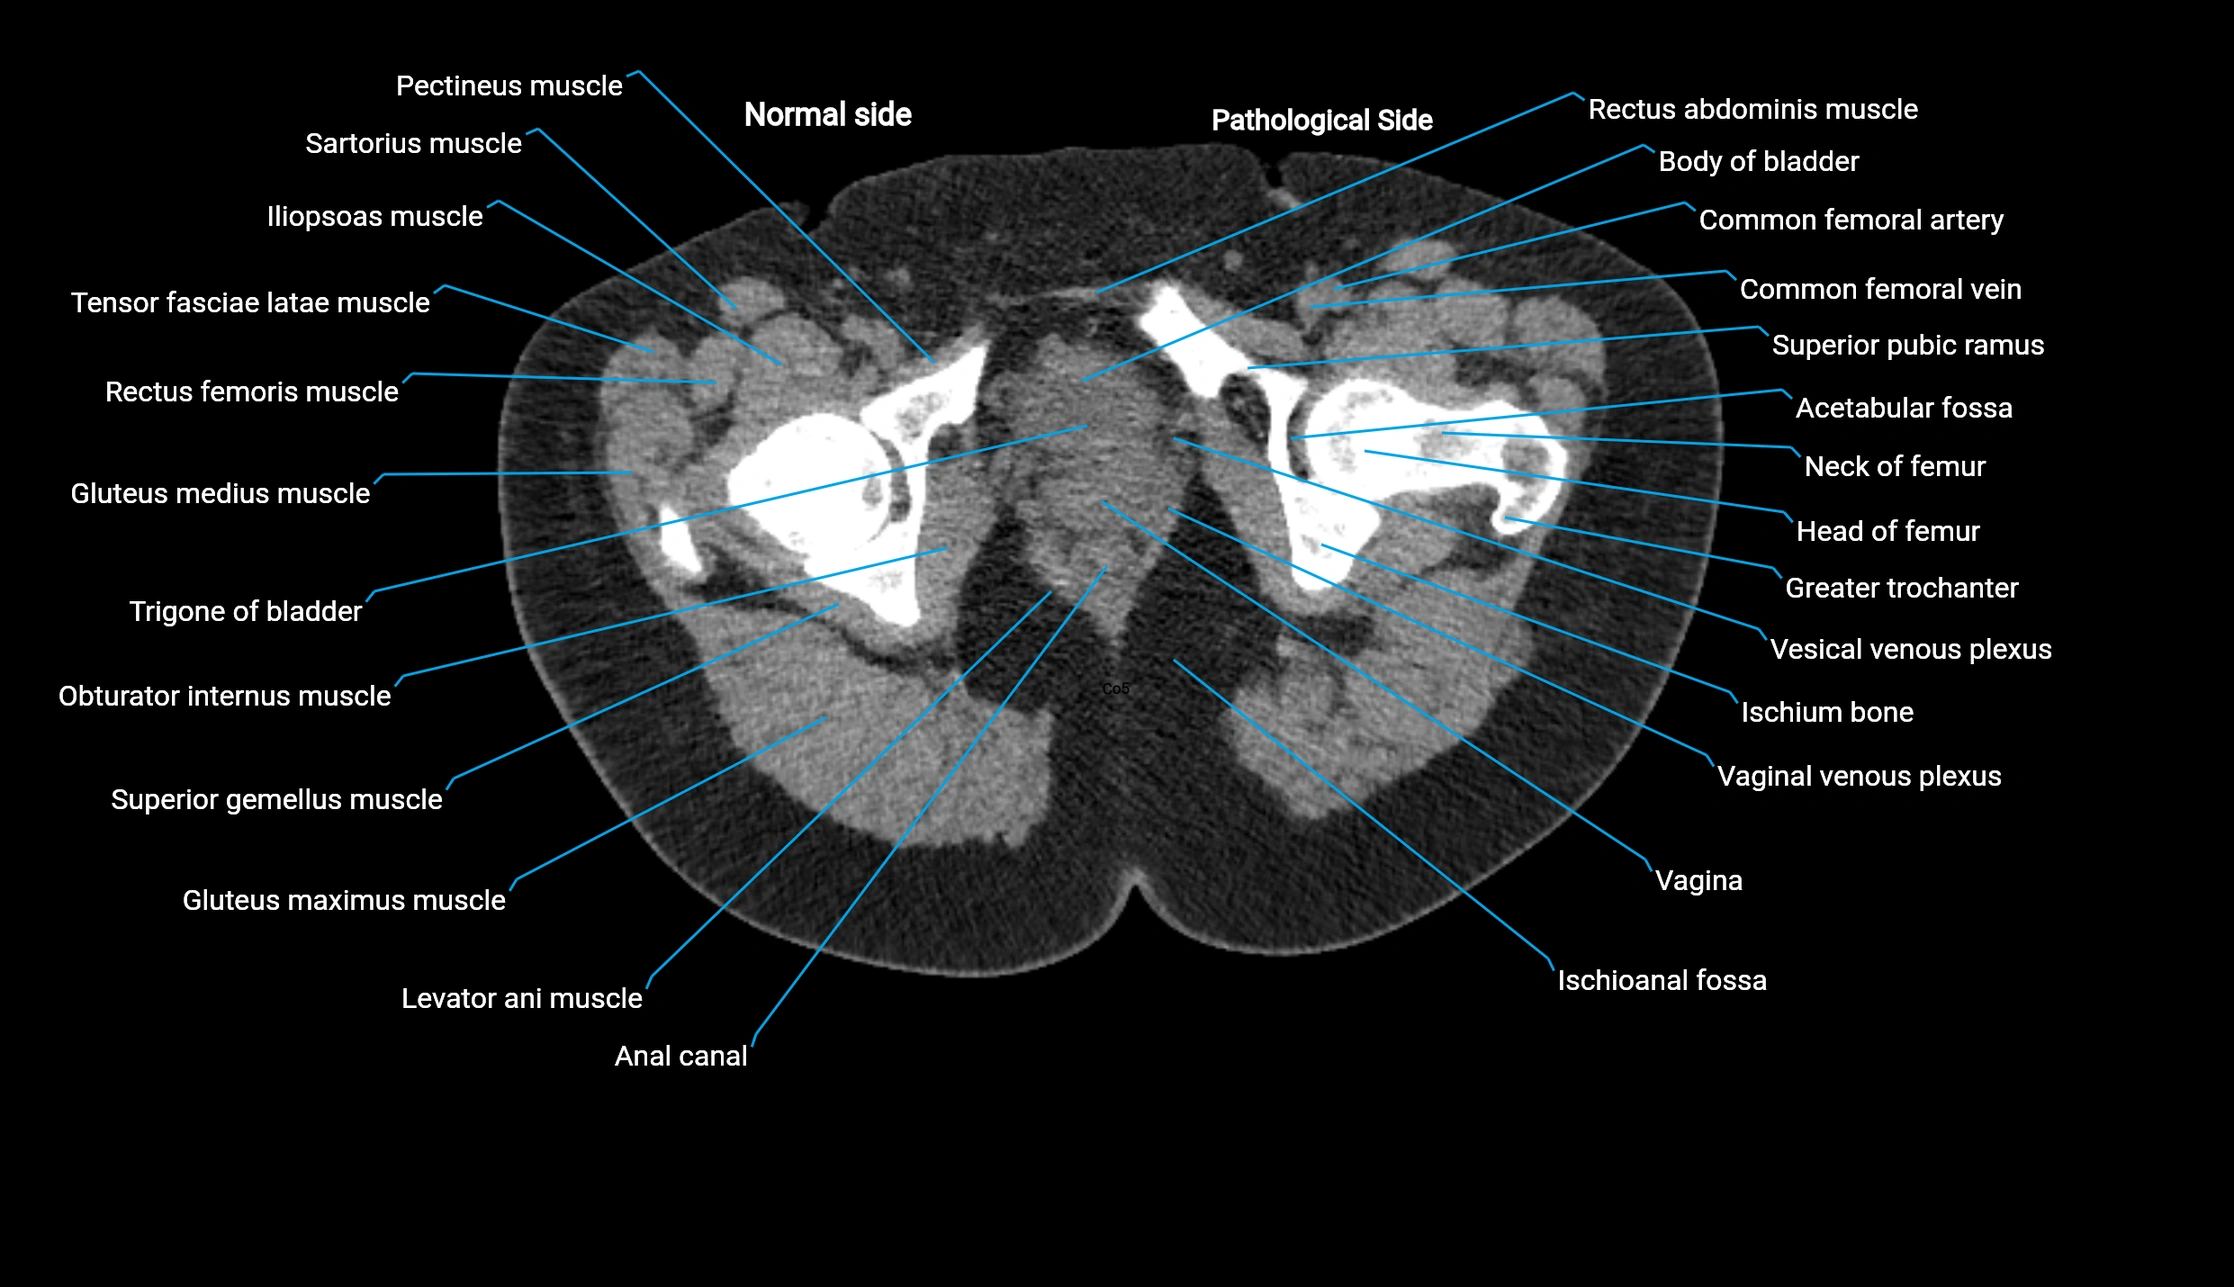

CT image

image